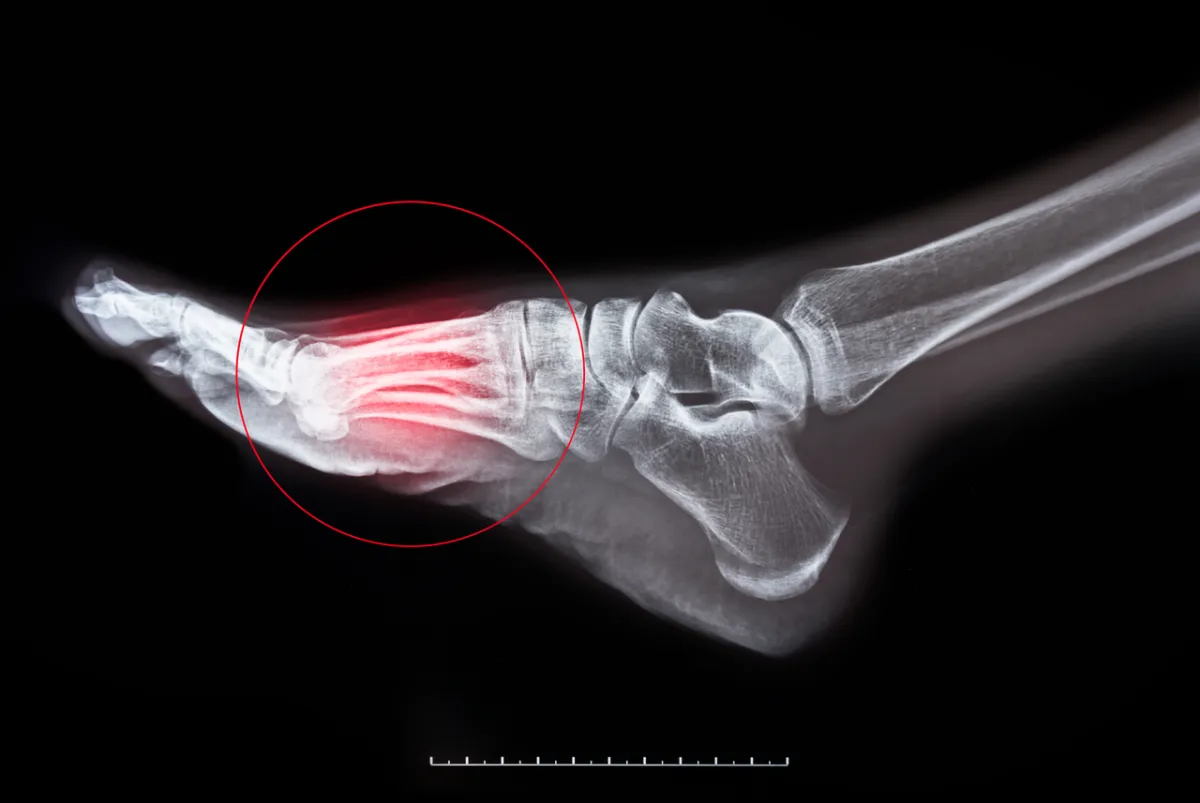

- ويتم من خلال هذا الاستخدام، الكشف عن صور للأنسجة والأعضاء والعظام والأوعية الخاصة بجسم الإنسان، ويقوم أطباء وأخصائيو الأشعة بتفسير تلك الصور التشخيصية، وبالتأكيد يعتمد العلاج على مدى دقة هذه الصور.

- وقد أصبح التصوير الإشعاعي أداة تشخيصية لا غنى عنها في الطب الحديث، حيث لم يقتصر الأمر على التشخيص فحسب، بل شهدنا حالات علاجية عديدة تخص المرضى؛ كإعادة تنظيم العظام المكسورة، واكتشاف مكان القرحة في الجهاز الهضمي، وعلاج العديد من الحالات والإصابات الشديدة، والكشف عن بعض أنواع السرطانات على سبيل المثال.